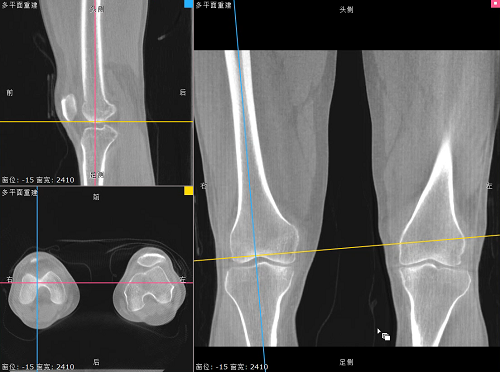

对于WR-3D技术的问世,主要解决了两大核心问题:1、解决了普放DR漏诊率高的现状,常规DR设备仅有某一角度的二维影像、密度信息极差,而WR-3D能获得更丰富的诊断信息,多角度拍摄三维重建影像,任意角度任意切面以及高敏感的密度信息;2、解决了CT无法获得立位(负重位)的三维影像,WR-3D无论是在断层图像重建、MPR多平面重建、VR体绘制都有着优异的表现,而对于临床诊断尤其是骨科,负重位的影像更具有临床价值。患者在负重位状态下肌肉状态、关节间隙及骨骼力线等都与患者平躺时是明显不同的。因此WR-3D在术前精准规划与术后精准评估方面有其非常重要的临床价值。

负重位状态下WR-3D MPR多平面重建